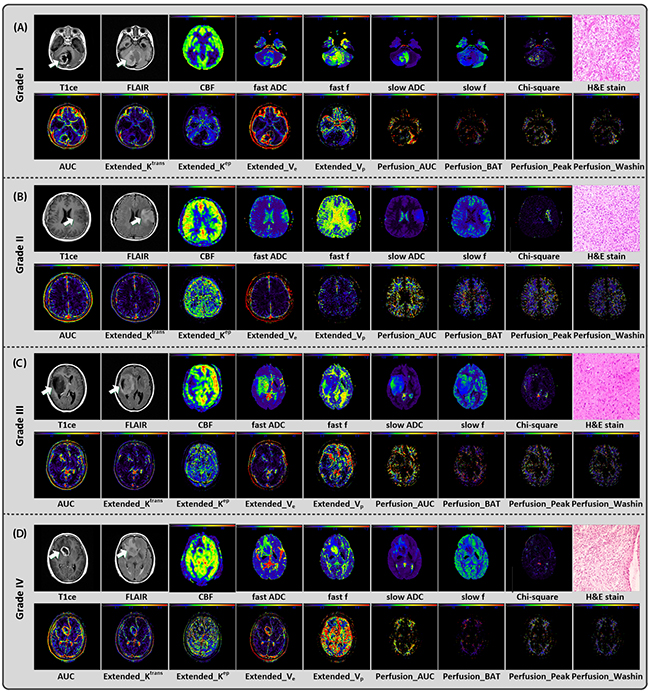

The example conventional, multi-parametric images and pathological haematoxylin and eosin (H&E) stain results of four individual patients diagnosed of WHO grade I, grade II, grade III and grade IV were provided in Figure 1. For each individual, conventional MRI images (T1ce/FLAIR), ASL parametric map (CBF), DWI parametric maps (fast ADC, fast f, slow ADC, slow f and Chi-square) and part of DCE parametric maps (9 out of 24 parameters, i.e. AUCAIF, “Extended_Ktrans, Extended_Kep, Extended_Ve, Extended_Vp, Perfusion_AUCEP” Perfusion_BAT, Perfusion_Peak, and Perfusion_Washin) were figured for the selected slice with glioma. The H&E stain results demonstrated that the HGG gliomas (grade III and grade IV) had relatively high cell density (see Supplementary Figure 1).

Figure 1: Conventional/multi-parametric MRI maps and H&E stain results of 4 individuals diagnosed as grade I (A), II (B), III (C), and IV (D) gliomas, respectively. For each individual, 1 parametric map derived from 3D ASL (i.e. CBF), 5 parametric maps derived from multi b-value DWI (i.e. fast ADC, fast f, slow ADC, slow f and Chi-square maps), part of parametric maps derived from DCE (9 out of 24, i.e. AUCAIF, Extended_Krans, Extended_Kep, Extended_Ve, Extended_Vp, Perfusion_AUCFP Perfusion_BAT, Perfusion_Peak, and Perfusion_Washin) and H&E stain (i.e. haematoxylin and eosin) result were shown.